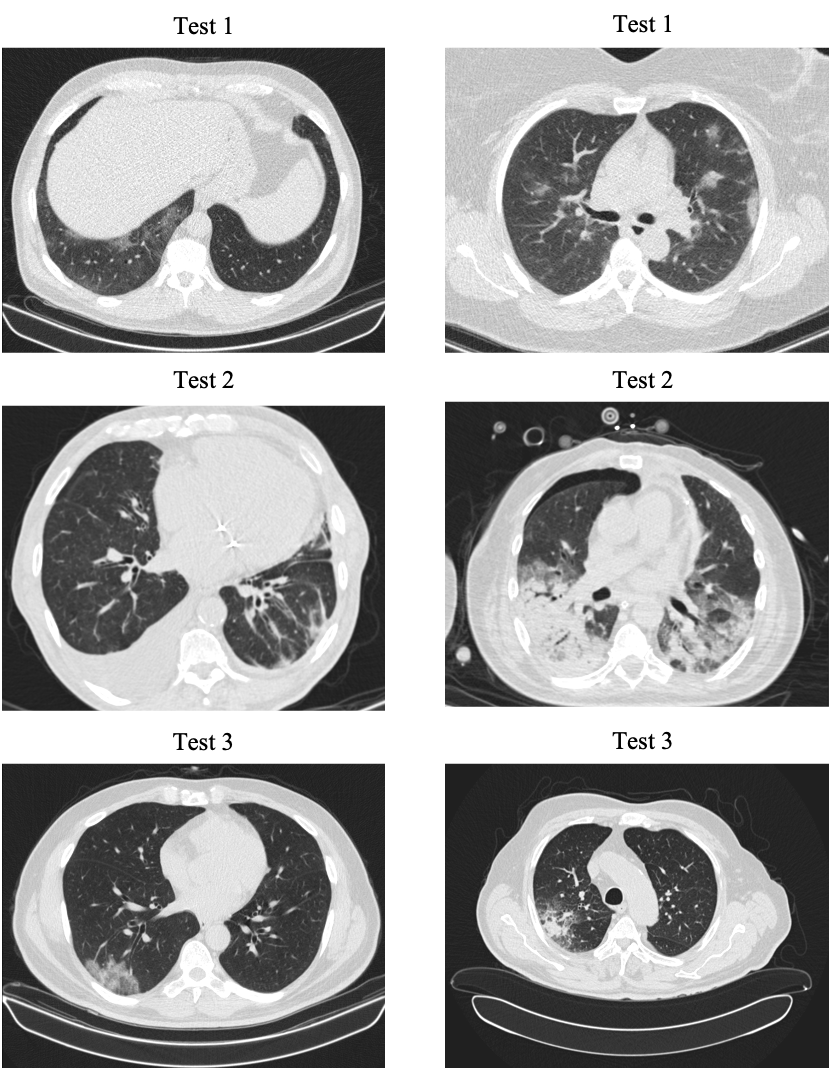

Additional statistical and demographic information about different train and test sets used in this study are provided in Table 3. In Table 3, Center 1 represents the Babak Imaging Center and Center 2 is the Tehran Heart Center. Both imaging centers are located in Tehran, Iran and use the Filtered Back Projection reconstruction method [38] to obtain the CT images. Sample CT slices from the first three test sets are shown in Fig 2. Various scanning protocols and settings have been used to obtain the train and test datasets used in this study. The important parameters that contribute the most to the image quality and characteristics are presented in Table 1.

Refer to caption

Fig 2: Sample CT slices from the first three test sets. In Test set 1, the noise level is high. In Test 2, some cases reveal cardiovascular-related complications. In Test 3, the image quality and contrast are higher compared to other test sets.